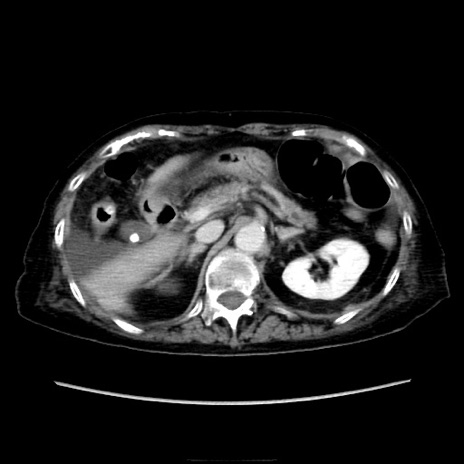

症例40(横断像)

横断像